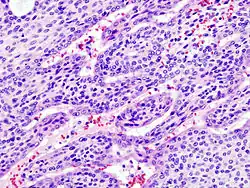

Bajo el microscopio, tienen una apariencia altamente variable, incluso dentro de un mismo tumor. Clásicamente, es un tumor bifásico y se caracteriza por tener una mezcla de epitelio poligonal y elementos mioepiteliales de forma de huso en un trasfondo de estroma muy variable que puede ser mucoide, mixoide, cartilaginoso o hialino.[1] Los elementos epiteliales pueden acomodarse en forma de estructuras ductales, o bien en forma laminar, agrupados o en filamentos que se entrelazan. Las células que conforman el epitelio son de dos tipos, luminales (epiteliales) y no-luminales (mesenquimatosos) y pueden también ser poligonales, laminares o estrellados (por ello el término pleomórficos). Puede haber presentes áreas de metaplasia escamosa y perlas epiteliales.

El tumor no está envuelto, pero está por lo general rodeado de una seudo-cápsula de grosor variable. El tumor se extiende en sus dimensiones a velocidades variables, entrando en el parénquima glandular normal, formando un frente de forma de dedo, aunque ésta variación no implica una transformación maligna.